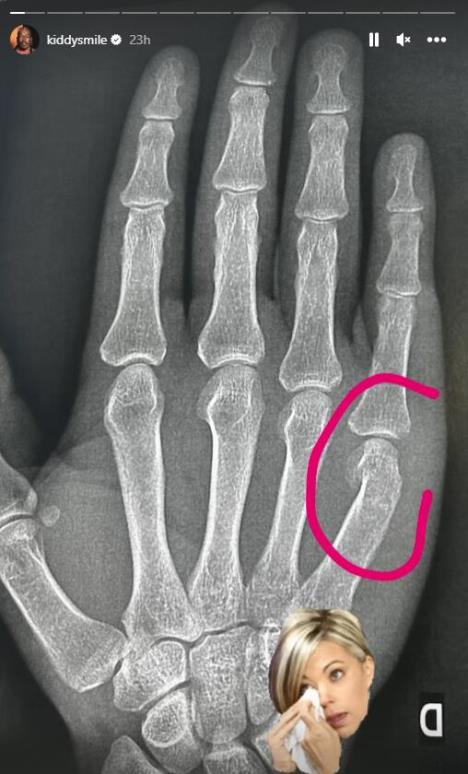

Pjer Haše, poznatiji pod umetničkim imenom Kidi Smajl, oglasio se na društvenim mrežama nakon incidenta na festivalu u Tisnom. Muzičar je objavio i fotografije na kojima se vidi slomljena ruka i da je potražio pomoć lekara.

- Mislim da je bitno da se zna šta se dogodilo. Osećanja su mi pomešana, a ruka slomljena. Hrvat je mog prijatelja nazvao pogrdnim imenima zbog njegove seksualne orijentacije. Muškarac ga je napao, a on je već imao loš dan. Prišao sam mu i pitao zašto je prozivao mog prijatelja - navodi Kidi Smajl.

- Muškarac je imao narukvicu za izvođače pa sam ga pitao s kim je došao. Počeo je da se dere na mene i onda me je udario. Pokušao sam da ga zaustavim, ali me udario još jednom. Tada sam izgubio kontrolu i srušio sam ga na pod. Došlo je obezbeđenje koje ga je smirilo. Bio sam jako uzrujan jer sam bio na lepom festivalu i super sam se provodio sa svojim prijateljem. Ne mogu da verujem da sam napadnut zato što sam homoseksualac. Primio sam dva udarca jer sam razmišljao o tome u kakvu ću se poziciju dovesti kao izvođač ako udarim nekoga na festivalu, a pri tome sam druge rase i kvir - dodao je di-džej.